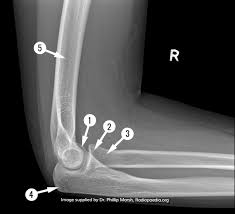

all of the following regardin the 45 degree medial oblique positions of the elbow are true exceot….

1)the coronoid process of the ulna is in profile

2)the olecranon process of the ulna is visualized within the olecranon fossa of the humerus

3)the radial head and capitellum of the humerus are free of superimposing structures

4)when positioning the patuent the hand is pronated

3